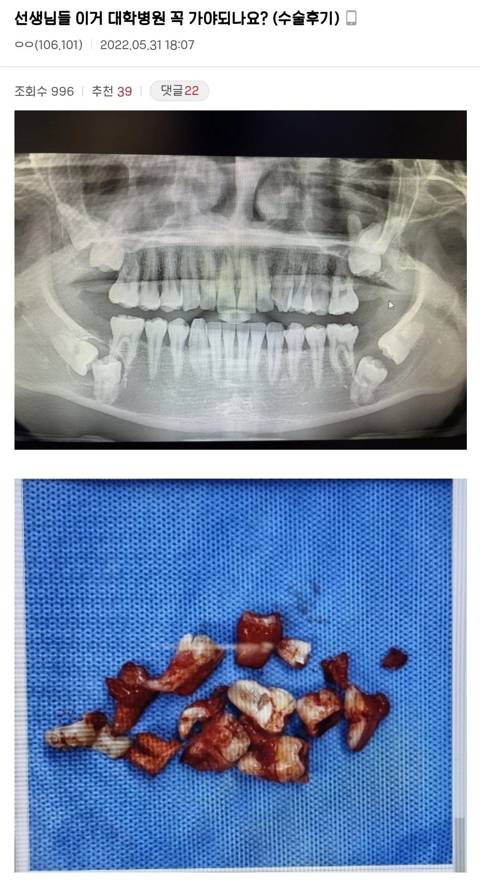

선생님들 이거 대학병원 꼭 가야하나요? 역대급 사랑니 수술후기

사랑니 마이너 갤러리

발치 사진있음

사랑니 8개가 아니고 사랑니 4개에 어금니도 못 나오고 묻혀있는 상태 + 낭종

3시간 수술 끝에 8개 모두 발치